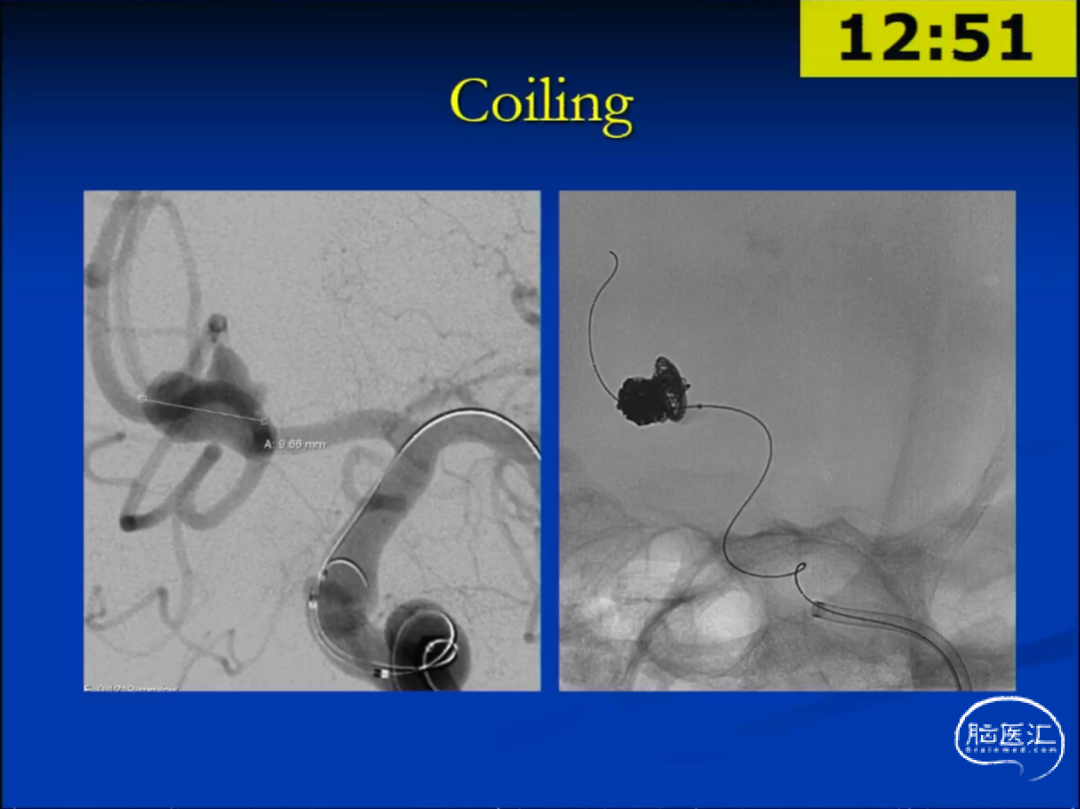

举例说明,70岁女性,11mm的前交通动脉动脉瘤(未破裂型),宽颈,形态不规则。

对于该动脉瘤,使用FD有较大的覆盖侧枝血管(Jailing)的风险。最终选择了球囊辅助的弹簧圈栓塞术,达到了完整的栓塞。

弹簧圈的优势在于其可塑性性,而球囊/支架辅助弹簧圈技术可以减少弹簧圈的逃逸。